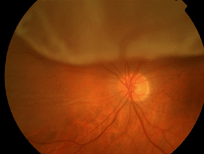

Media opacity: Cloudiness in the normally clear parts of the eye

The 2 parts of the eye responsible for focusing light are the cornea and the lens.

In some children, either the cornea or the lens can become cloudy and cause less light to be able to reach the back of the eye.